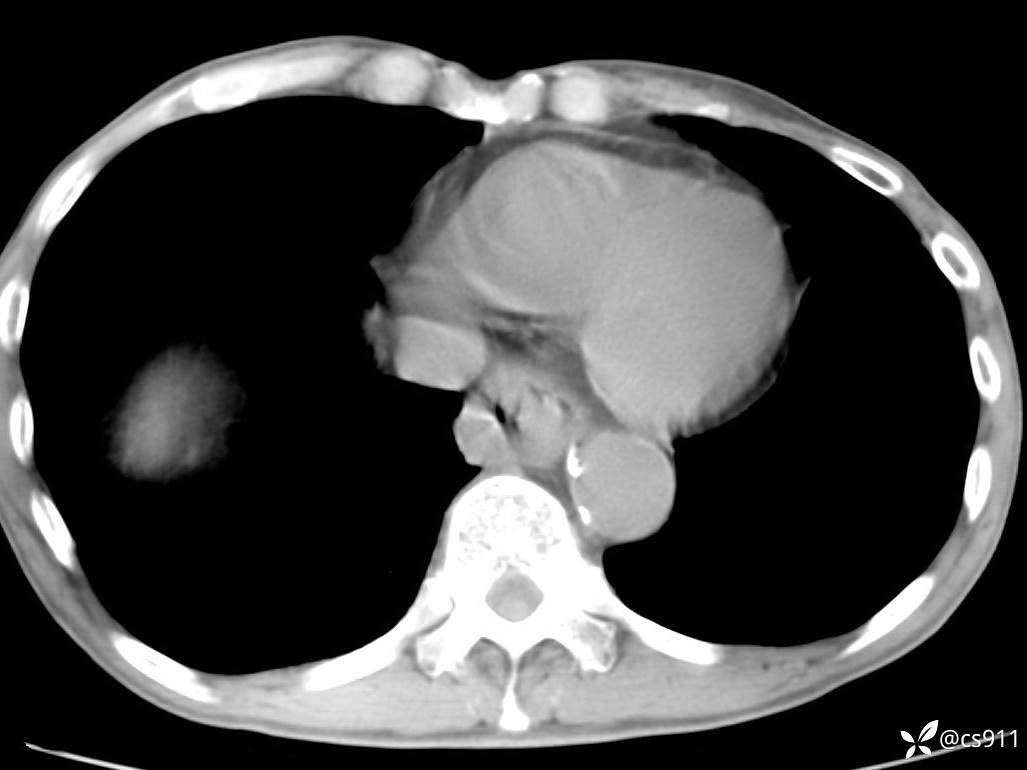

急腹症之急诊CT,原因?答案公布

男,77岁,腹痛、腹胀伴恶心呕吐1天。呕吐胃内容物,非喷射性呕吐,有咖啡色样胃内容物,诉有胃穿孔病史。查体:全腹平,下腹部压痛,全腹无反跳痛,叩诊呈浊音,移动性浊音阴性,肠鸣音减弱,1-2次/分。肛检:直肠未扪及明显肿物,可触及大量粪块。

血淀粉酶(AMY) HH 1859 U/L 35-135